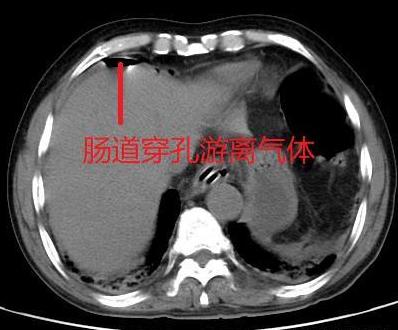

迄今为止,超声和MRI对气体的观察是弱项,将它们用于诊断胃肠道穿孔不合适。但CT观察气体很敏感,所以说,胃肠道穿孔先做CT没有问题。

CT在肝前间隙中见到游离气影,提示胃肠道穿孔

当然,我们不要忘记了前面说过的CT检查,CT观察气体比X线摄片敏感些,即使是患者平卧,也有可能在肝脏前、肠系膜间或肾旁前间隙内见到胃肠外的少量气体影,从而确定诊断。